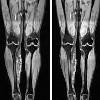

МРТ мягких тканей конечности

МРТ мягких тканей конечности – современный высокоточный метод исследования, в ходе которого проводится сканирование тканей в условиях магнитного поля высокой напряженности. Осуществляется с использованием или без использования контрастного препарата. Всего в Казани найдена 1 клиника, где можно сделать МРТ мягких тканей конечности.